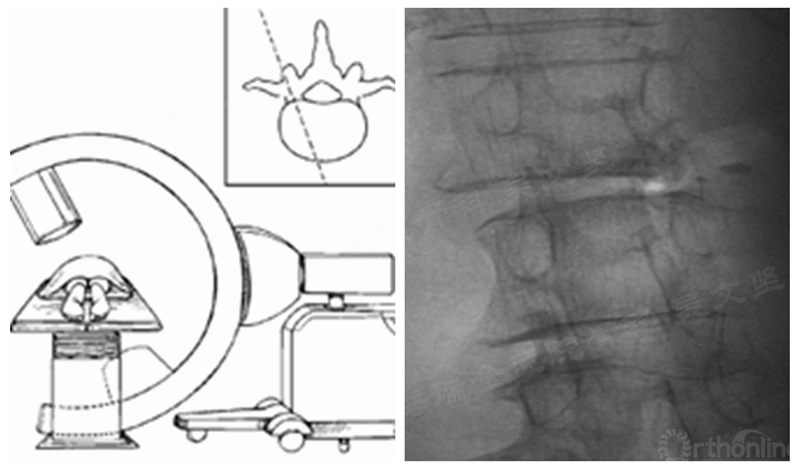

一般情况下,我们获得的正位片实际上并不是椎弓根的正位片。少数情况下,我们可能需要调整透视方向获得椎弓根的En Face view (正前位片)。(图2)

图2 En Face view